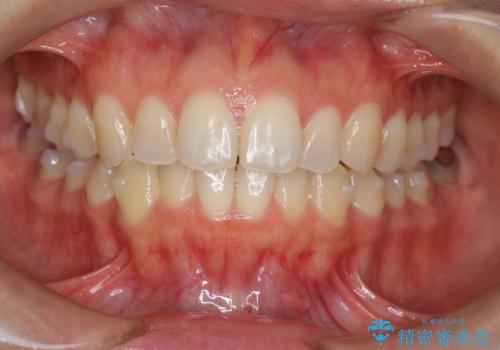

前歯のがたつきをしっかり治すマウスピース矯正

- 前歯のガタガタをきれいに並べたい、と希望され来院されました。

マウスピース矯正インビザラインのクリンチェックを用いて治療前にしっかりと歯並びのゴールのシミュレーションを行い、治療を開始します。

がたつきのないきれいな歯並びに仕上げることができ、満足いただくことができました。